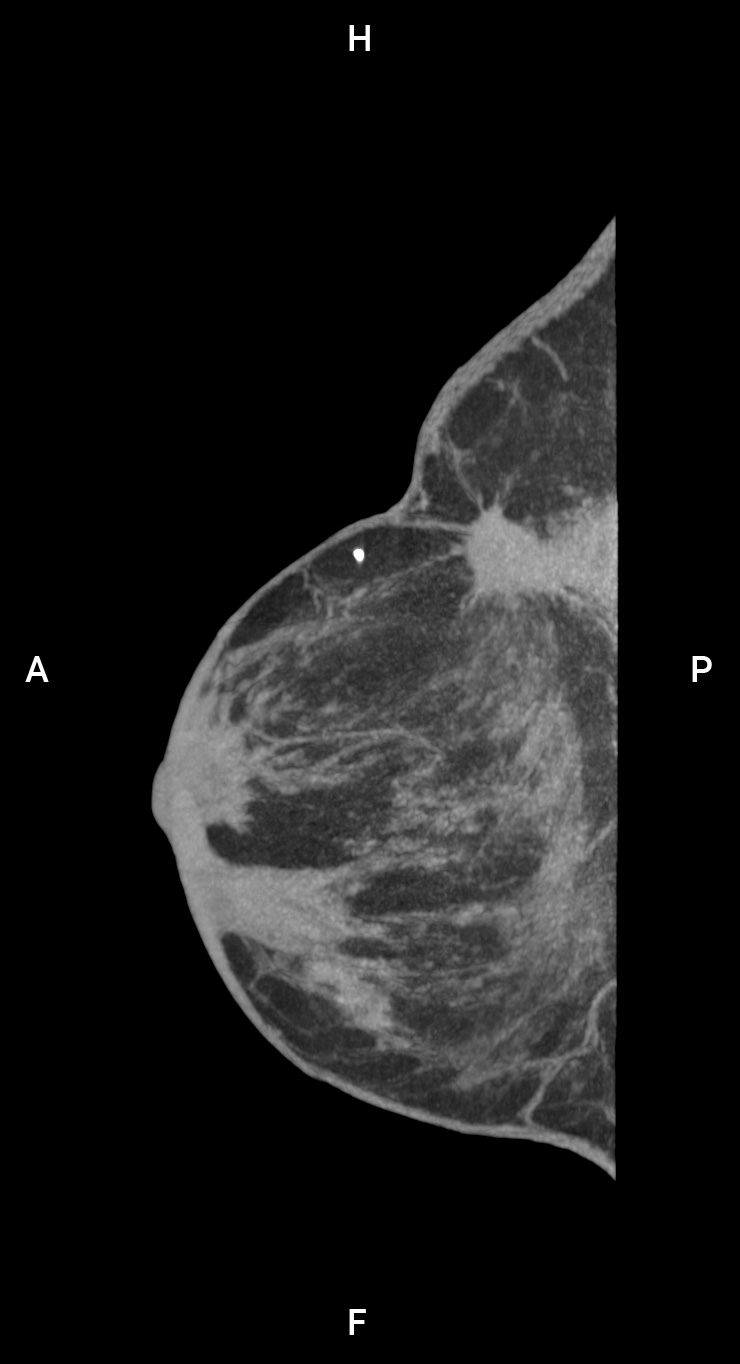

评估: BI-RADS 4/组织学:镰状腺病

图片来源:Prof: Prof. Dr. med. Andreas Boss (USZ - 苏黎世大学医院)